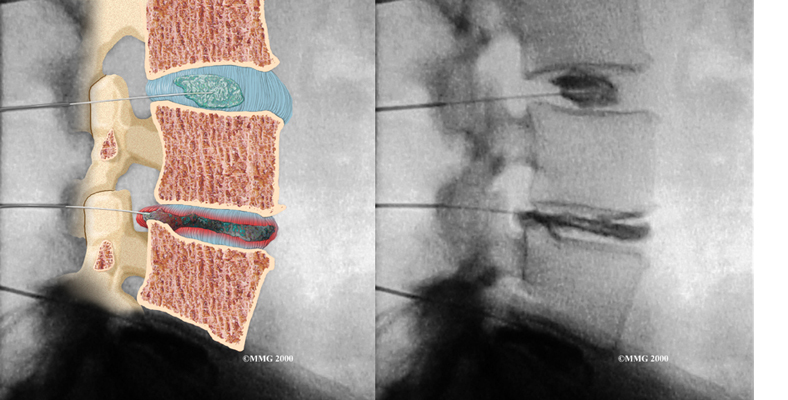

Doctors sometimes order a specialized X-ray test called . In this test, dye is injected into one or more discs. The dye is seen on X-ray and can give some information about the health of one or more discs. This test may be used when surgery is being considered to determine which disc is causing problems.